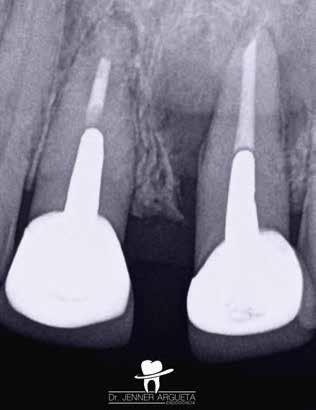

11. a–c. ábrák: A jobb felső nagymetszőfog (1.1) kezelése során készült radiológiai felvételek. Kiindulási röntgen: jól látható a gyökér-reszorpció és a gyökér oldalán elhelyezkedő radiolucens terület (a). A teljes munkahosszon levezetett mester poénról készült felvétel (b). Az endodonciai ellátás befejezését követően készített felvétel (c).

zárás során EQ-S eszközzel (Meta Biomed) szónikusan aktivált CeraSeal pasztát használtunk (10. ábra). A második ülés megkezdésére a reszorbeálódott területre helyezett anyag teljesen megkeményedett, és ezáltal lehetővé vált a gyökérkezelő tűk gyökércsatorna lumenének teljes hosszán történő végigvezetése. Az endodonciai kezelés befejezésekor szintén a CeraSeal anyagot használtuk sealerként (11. a–c. ábrák)

A hároméves kontroll alkalmával készített röntgenfelvételen a korábban a gyökér laterális részén elhelyezkedő radiolucens elváltozások teljes regenerációját észleltük (12. a–c. ábrák)